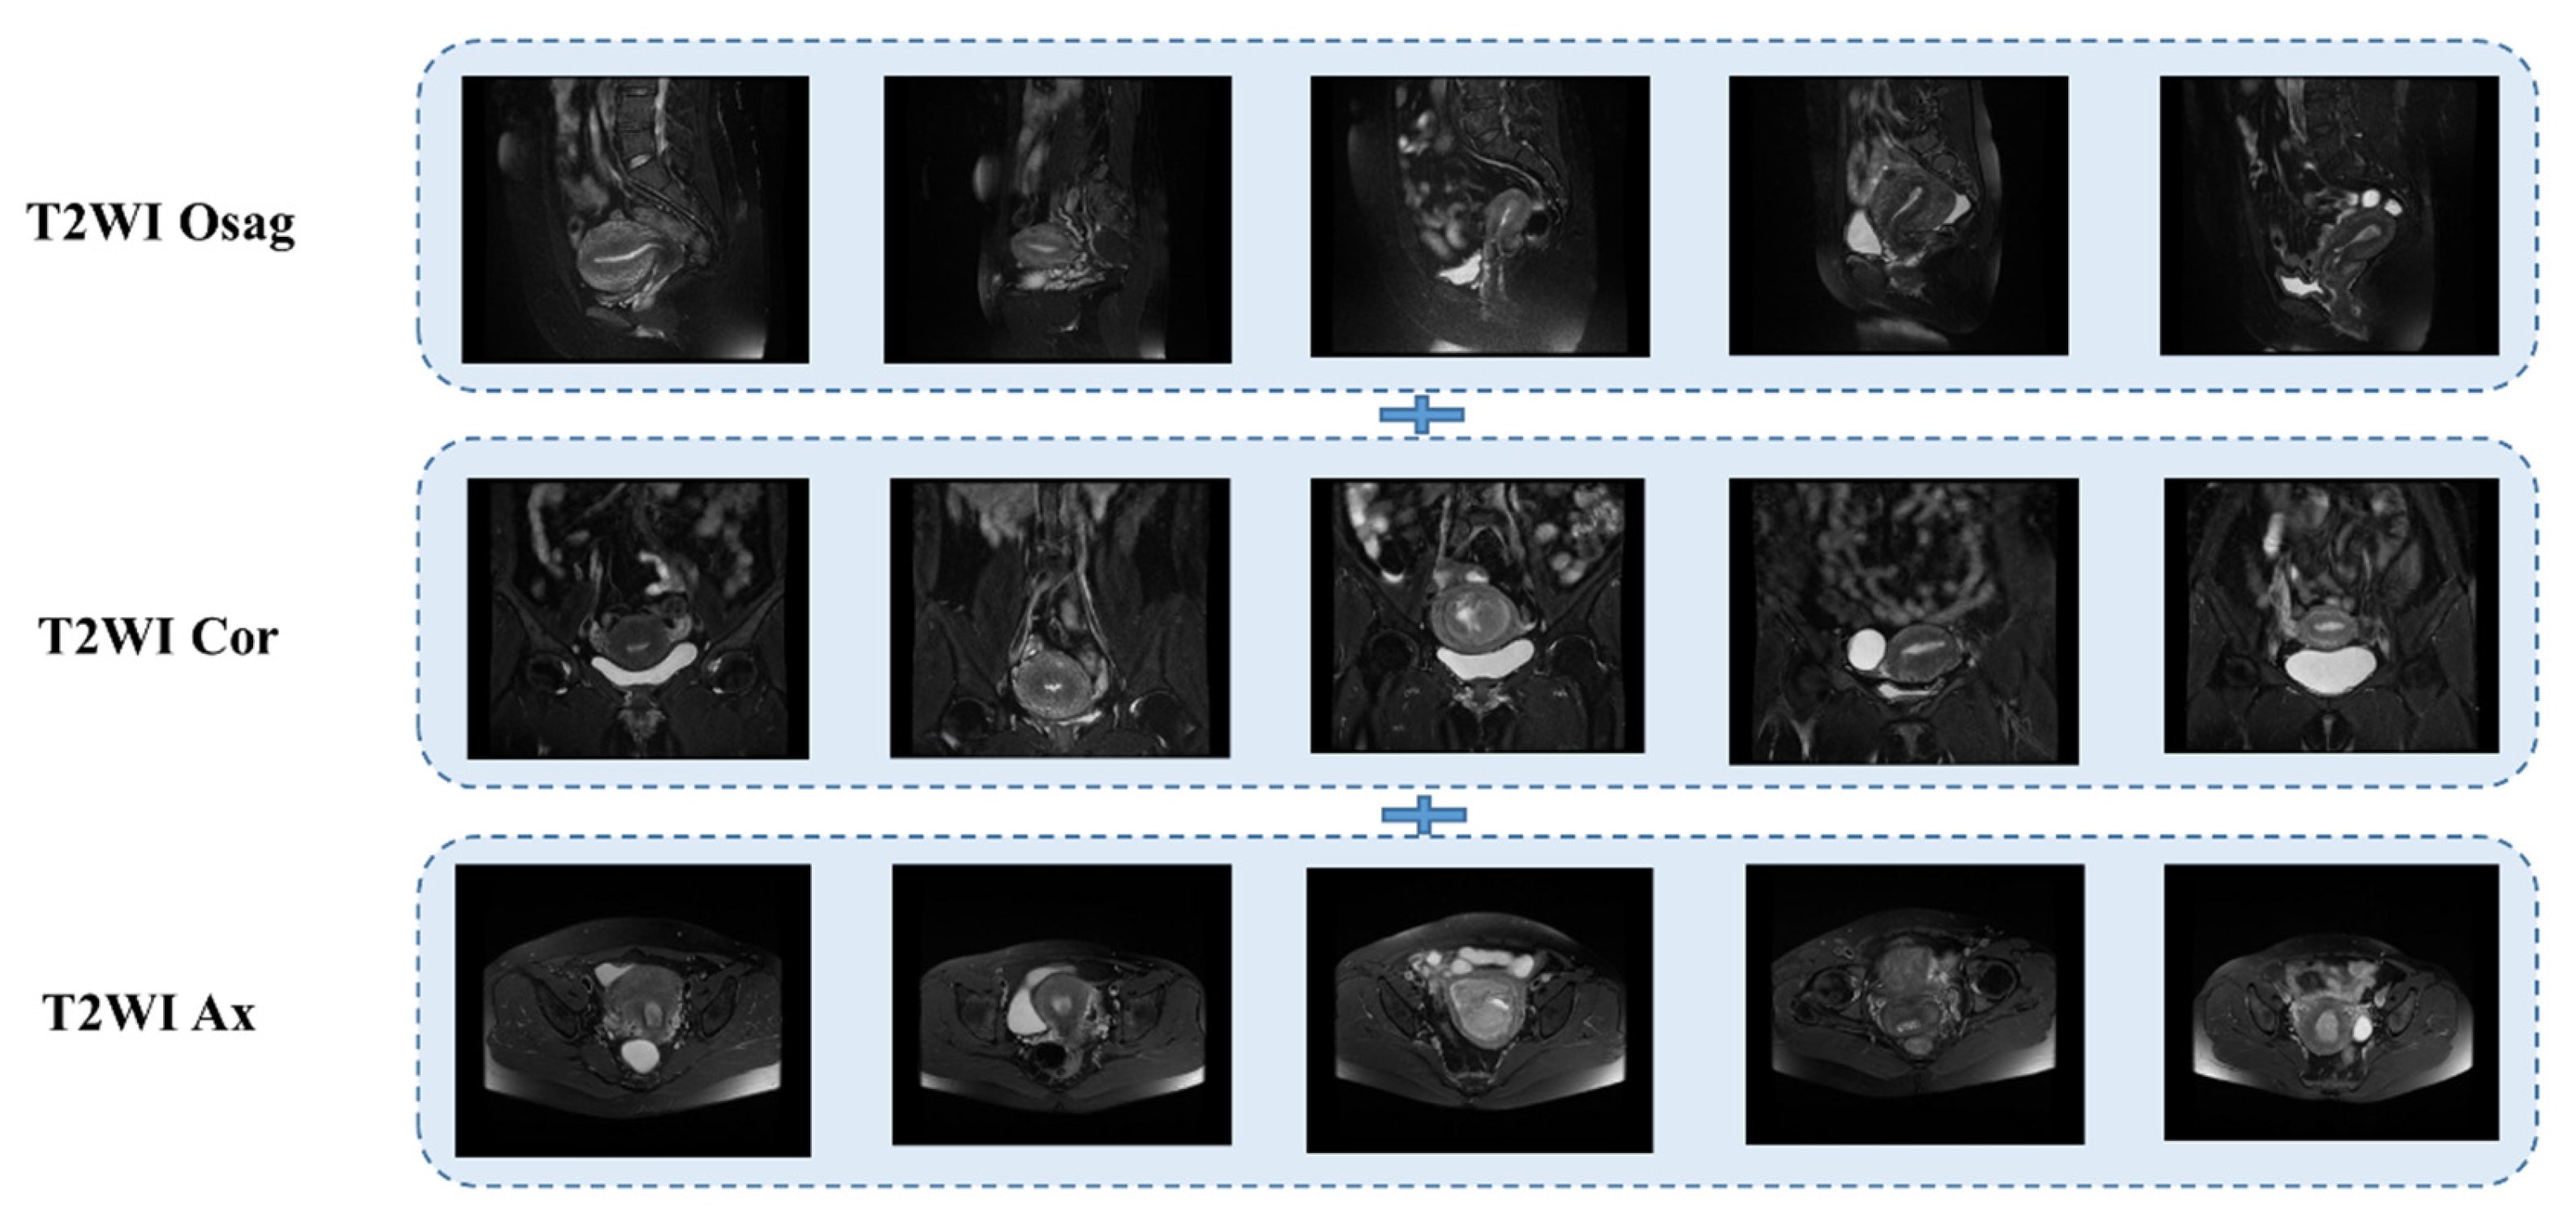

The T2WI sequence was one of the first sequences chosen by radiologists for MRI of patients with endometrial cancer [25,26]. It provides clear imaging with high resolution and allows clear differentiation of the molecular uterus, myometrium, and endometrial layers for staging. Conventional uterine T2WI can realistically show the three-layer structure of myometrium (proliferative stage—medium signal, secretory stage—high signal, postmenopausal stage 3- signal weakening and atrophy), myometrium conjugate (medial portion of myometrium, smooth muscle structure is tight, about 2~8 mm low-signal bands), and endometrial cavity (high signal). Some use a single sequence plane to extract tumor features [27,28,29]; in this case, we used three planes, the sagittal, coronal, and transverse T2WI, which are presented in Figure 3 below.

Figure 3. MRI T2WI sequence of endometrial cancer.